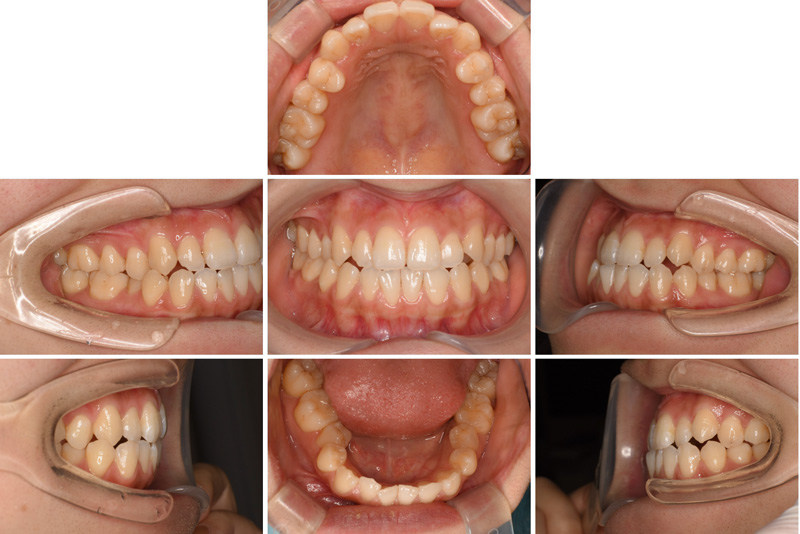

58歳女性

治療前

治療後

| 施術名 | インプラント治療 |

| 施術の説明 | インプラント治療とは、歯を抜いた所にチタン製の人工歯根を埋入し、新しく歯を入れる方法です。 |

| 施術の副作用 (リスク) | 腫れや疼痛を感じる、違和感を感じるなどの症状を生じることがあります。 |

| 施術の価格 | 53万円~+消費税 |